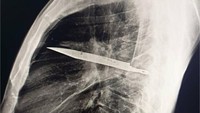

"Rontgen dada lateral awal menunjukkan adanya benda logam tersangkut di bagian tengah dada, dengan bayangan samar di sekitarnya yang mengindikasikan hematoma terlokalisasi kronis yang mengeluarkan cairan, atau fibrosis pasca-trauma, kemungkinan besar akibat luka tusukan pisau pasien," tulis dokter dalam studi kasusnya. (Foto: Journal of Surgical Case Reports)